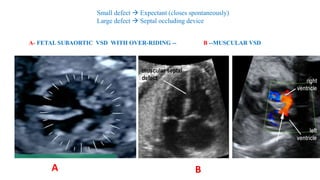

Small defect  Expectant (closes spontaneously)

Large defect  Septal occluding device

A- FETAL SUBAORTIC VSD WITH OVER-RIDING -- B --MUSCULAR VSD

A B